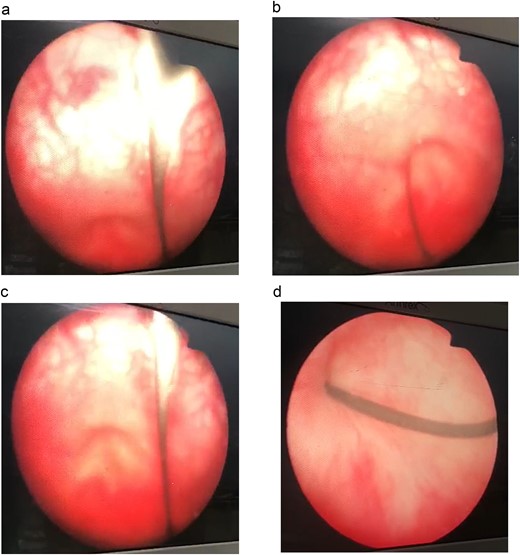

Her post-operative course was unremarkable. An evaluatory X-ray 3 days post-op revealed good outcomes (Fig. 2).